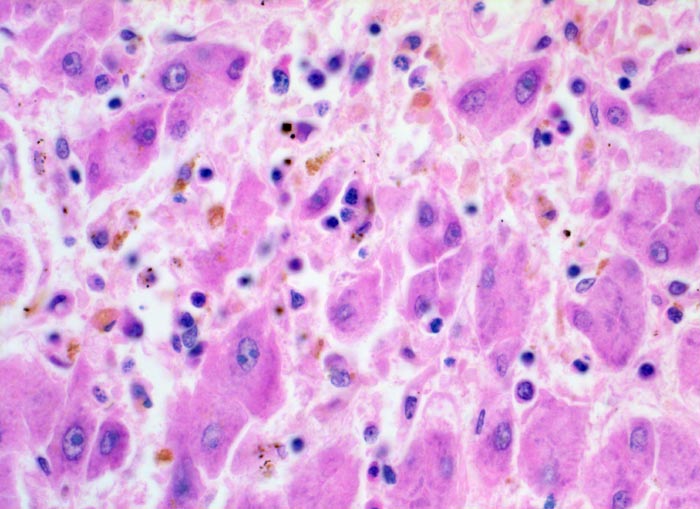

Das histologische Bild der akuten Hepatitis vom Virustyp ist gekennzeichnet durch eine lobuläre Entzündung bei fehlender portaler Fibrose und nur geringer entzündlicher Infiltration der Portalfelder. Es finden sich ballonierte Hepatozyten, Apoptosen (> 1164) und fleckige Nekrosen. Perivenuläre Nekrosen, Brückennekrosen oder konfluierende multilobuläre Nekrosen und eine läppchenzentrale Cholestase können vor allem in klinisch fulminant verlaufenden Fällen nachgewiesen werden. Zahlreiche Makrophagen, welche Diastase-PAS positives Zeroidpigment (> 4319) von phagozytierten nekrotischen Hepatozyten enthalten, zeugen im subakuten Stadium von einer abgelaufenen akuten Hepatitis mit Parenchymnekrosen. Eine Unterscheidung der verschiedenen Typen der viralen Hepatitis und einiger Formen medikamentöser Hepatitiden gelingt rein morphologisch aufgrund des unspezifischen Bildes meist nicht. Für eine ätiologische Klassifizierung sind zusätzliche klinische Angaben erforderlich (Anamnese, Medikamente, Serologie).

• Ansammlungen zeroidbeladener Makrophagen innerhalb von Parenchymnekrosen (abgebaute fleckförmige Nekrose).

• Apoptosen (hypereosinophile abgerundete Leberzellen).